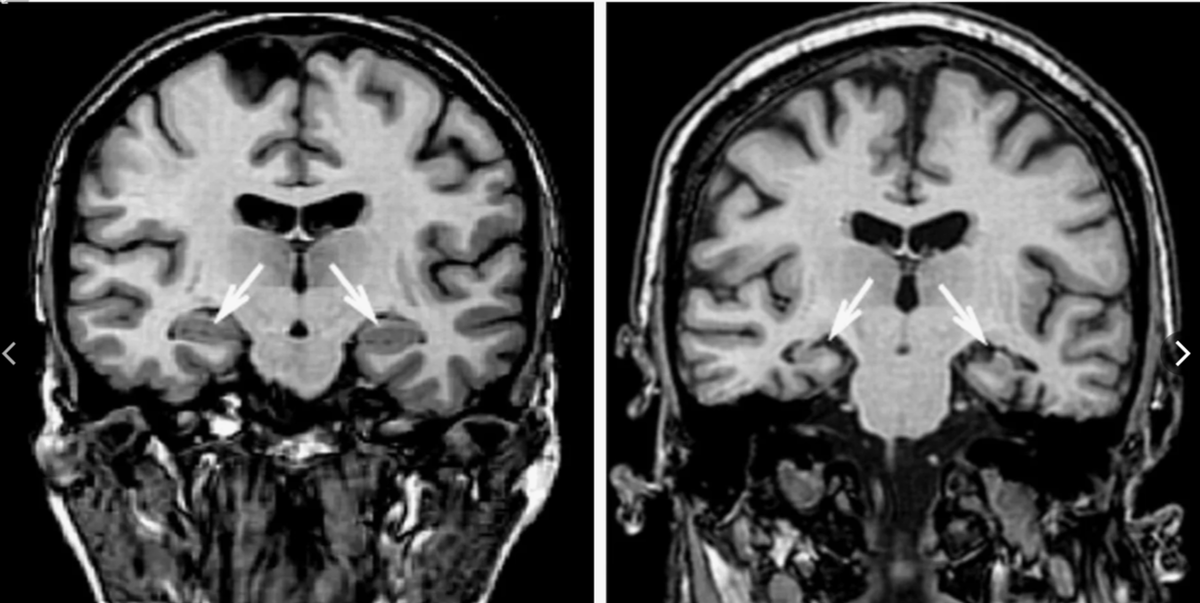

Тот факт, что гиппокамп играет важную роль в механизмах памяти, стало ясно после официально подтвержденной антероградной амнезии у Г.Молисона после резекции височной доли. Несмотря на то, что его кратковременная память не страдала, эксплицитная (сознательная) у него полностью отсутствовала.

Как я писала ранее, в мозге не существует конкретного отдела, отвечающего за память. Но гиппокамп играет в этом немаловажную роль. Позже было установлено, что он необходим для создания новых "указателей" воспоминаниям, а также поиска подходящего воспоминания с их помощью.